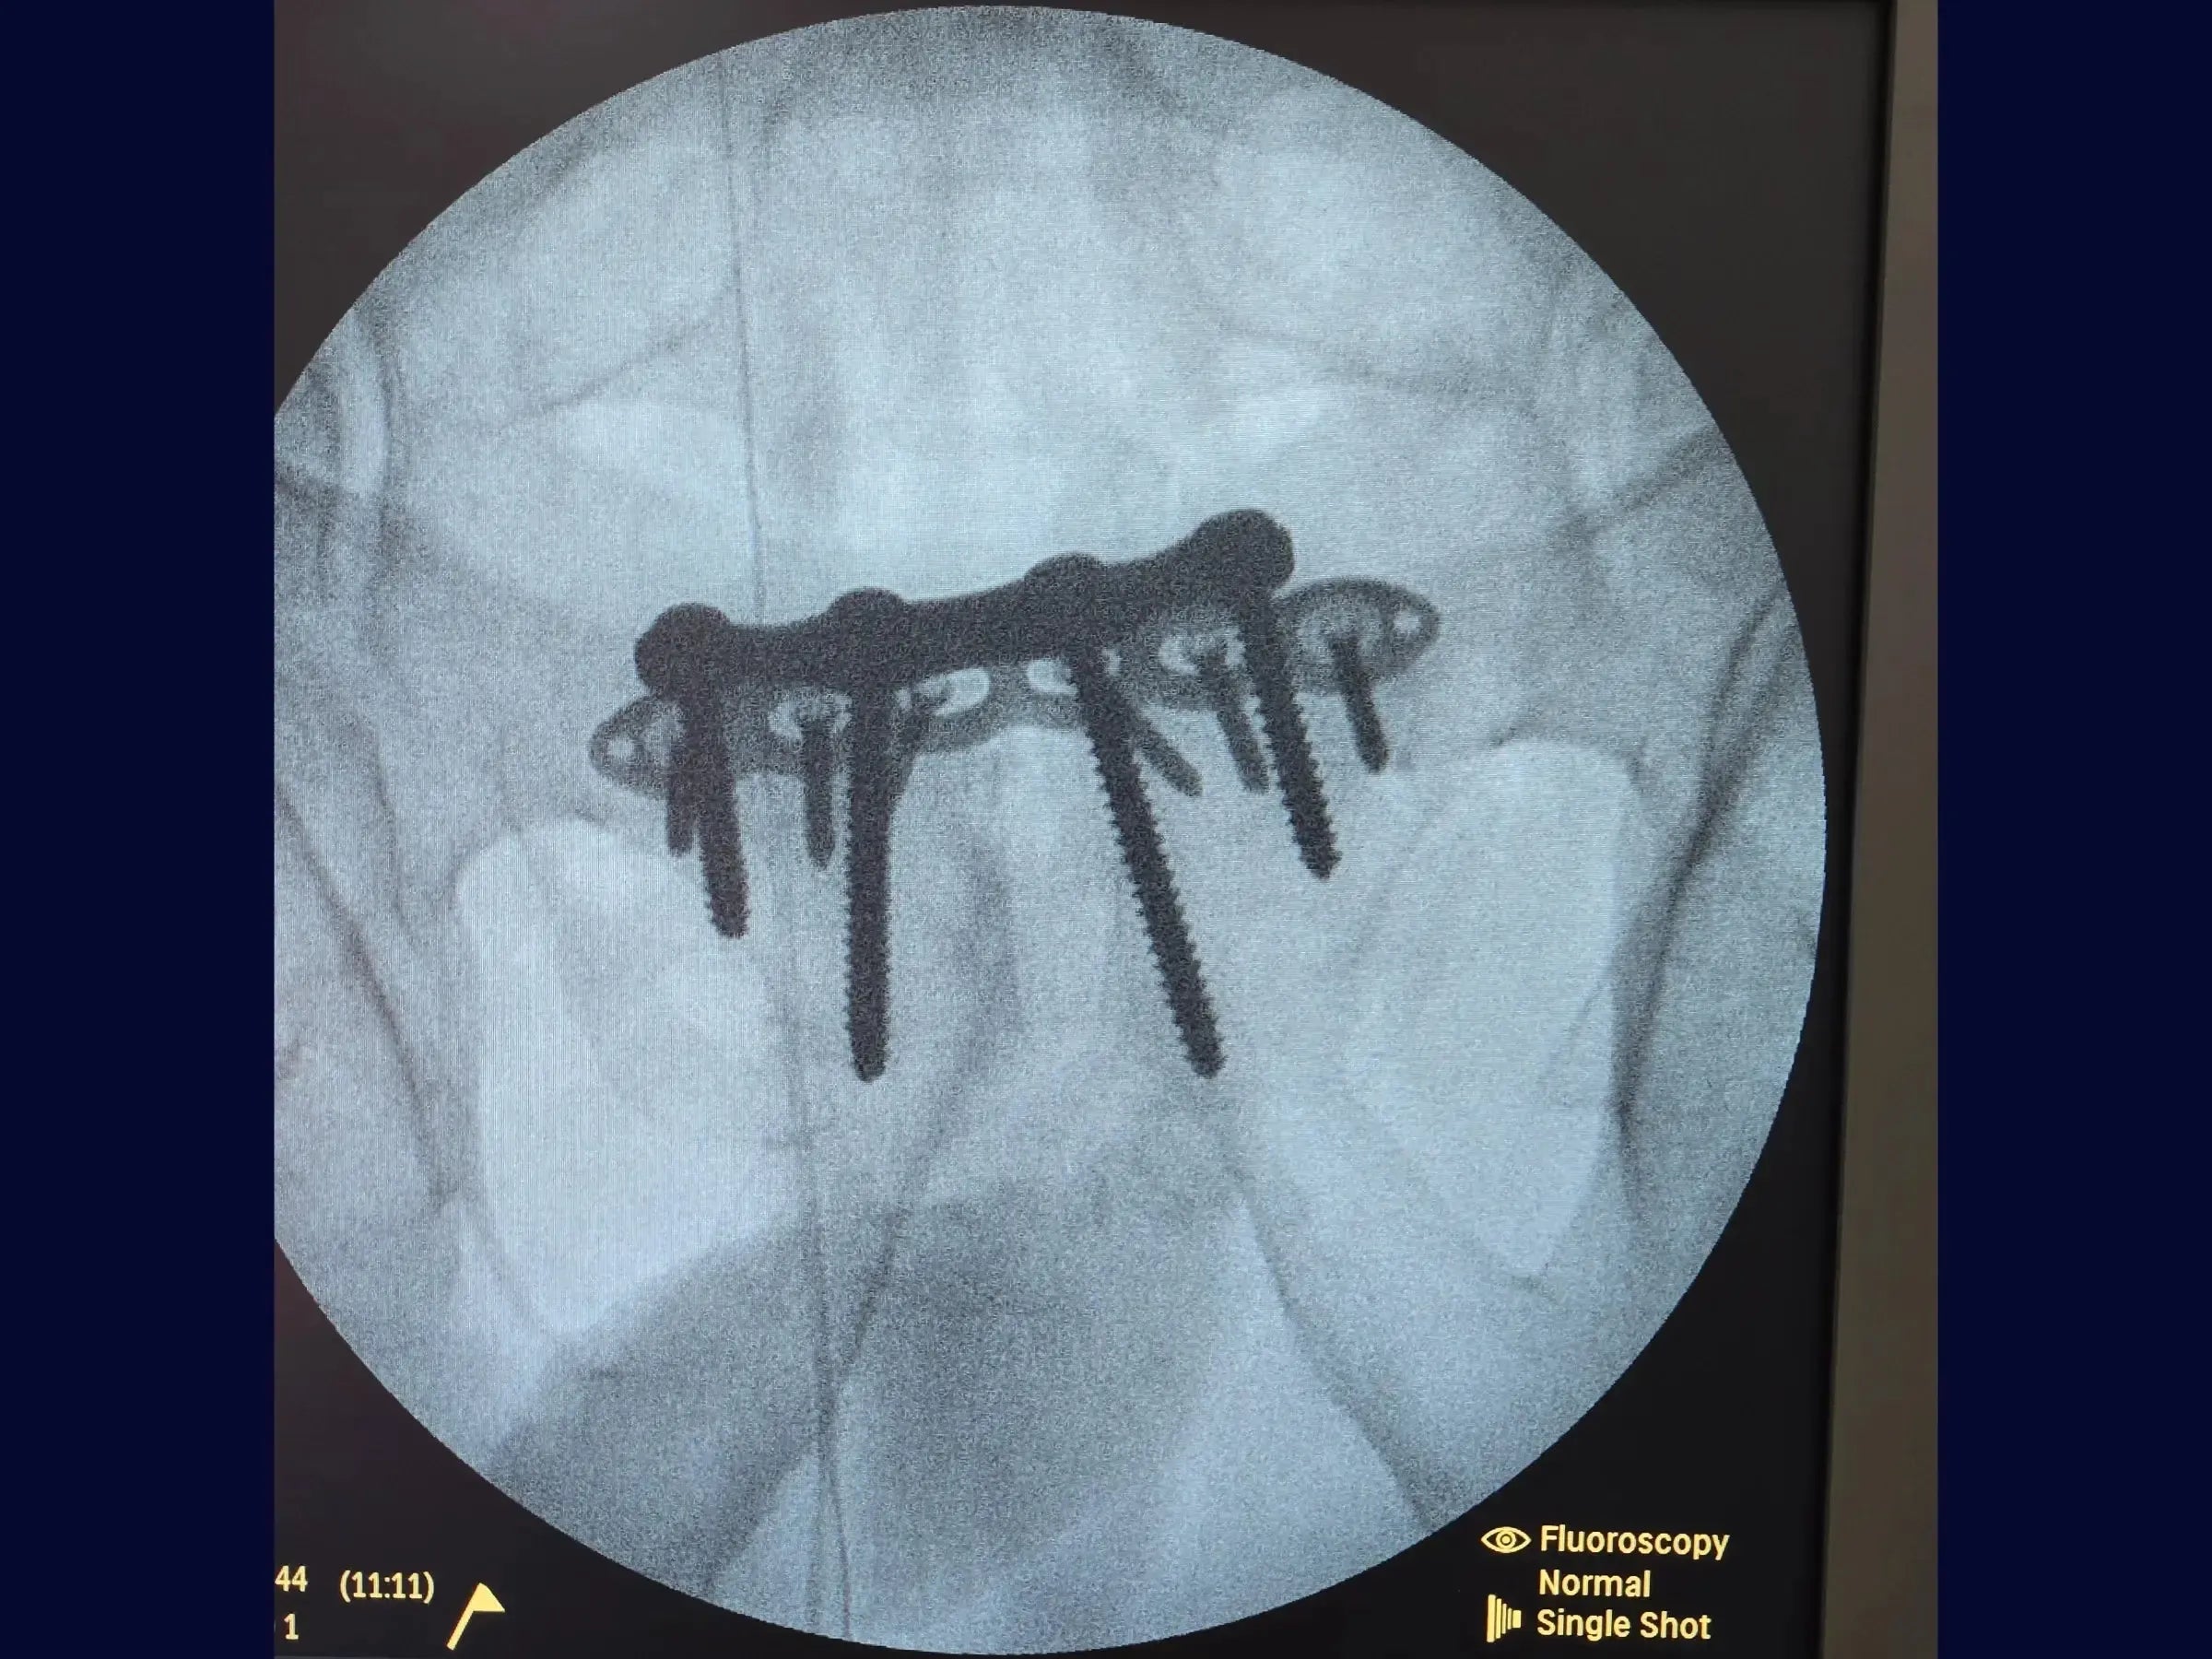

- Fixação Definitiva: Com a redução mantida, use uma placa específica para a sínfise com introdução dos parafusos em angulação de 30 graus. Se parafusos não bloqueados não estiverem firmes, adicione uma segunda placa bloqueada anteriormente para maior estabilidade.

- Aplicação de placas para fixação definitiva.